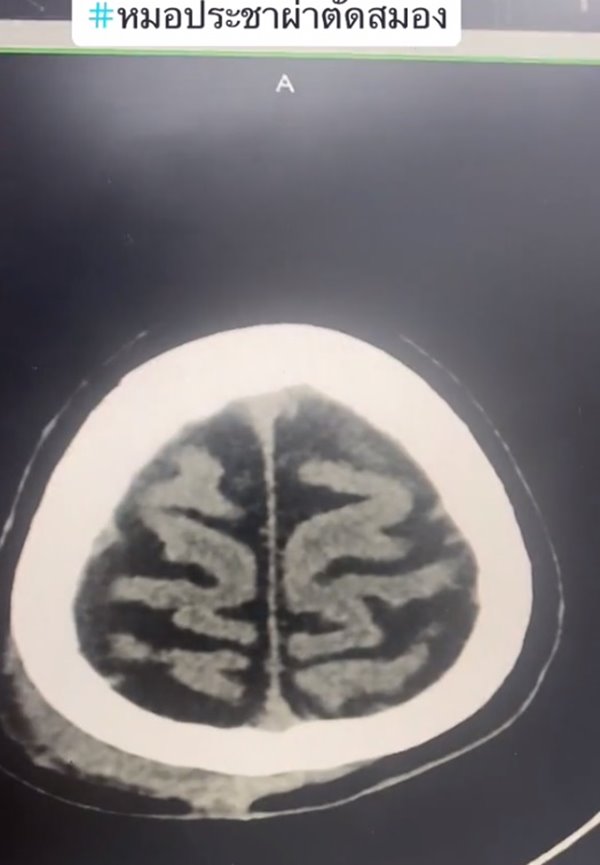

เปิดภาพเทียบให้ดูชัด ๆ สมองคนทั่วไปกับคนติดเหล้า เห็นภาพซีทีสแกนชัดเจน พบคนกินเหล้าจะมีอาการสมองฝ่อ ล้มนิดเดียวเลือดออกในสมอง ต่างกับคนทั่วไปชัดเจน ใครกินเหล้าต้องคิดให้ดี

เราอาจจะรู้กันว่า การติดเหล้านั้นมีผลทำให้เป็นโรคตับแข็ง และเป็นปัจจัยที่ทำให้เกิดโรคร้ายต่าง ๆ ตามมาได้มาก แต่ในความเป็นจริงแล้ว การดื่มเหล้าและมีอาการติดเหล้า ก็ส่งผลต่อสมองได้เช่นกัน และล่าสุดก็มีภาพซีทีสแกนมายืนยันในเรื่องนี้แล้ว

วันที่ 30 กรกฎาคม 2566 TikTok @doctor.pracha_neuro_surg ของ นพ.ประชา กัญญาประสิทธิ์ ประสาทศัลยแพทย์ มีการเล่าเรื่องราวประสบการณ์การผ่าตัดสมอง พร้อมข้อเตือนใจประชาชน โดยเปรียบเทียบกันระหว่าง สมองคนทั่วไปกับสมองคนที่ติดเหล้า มันต่างกันอย่างไรบ้าง คลิปนี้มีคนดูมากกว่า 1 ล้านครั้ง

หมอประชายังเล่าเพิ่มเติมว่า คนที่ดื่มเหล้าบ่อย ๆ เวลาล้มหัวกระแทก จะทำให้เลือดออกได้ง่าย เพราะเนื้อที่สมองน้อย ผลกระทบอื่น ๆ ก็ยังมีโอกาสเป็นเบาหวาน ไขมัน โอกาสอัมพาตจากสโตรก ดังนั้น มีโอกาสเสียชีวิตหรือพิการมากกว่าคนทั่วไป